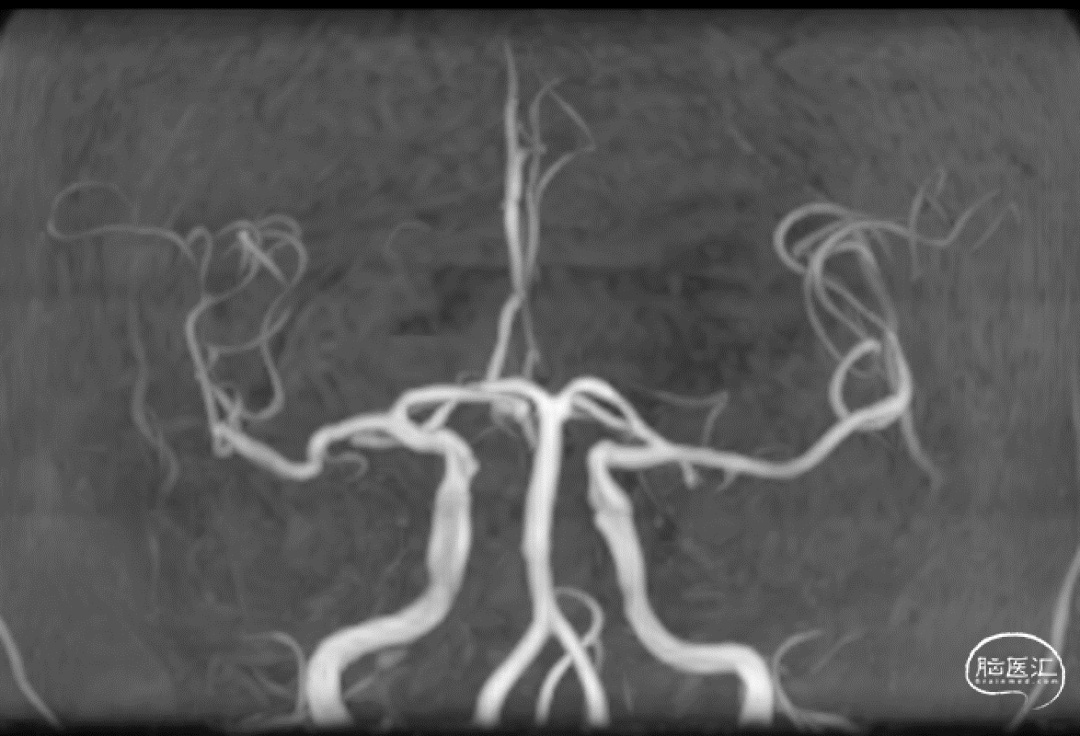

术前影像资料

急诊CT(2-22 3:00AM)。

入院前头颅MR(2-22 8:30AM)。

患者老年女性,既往心房颤动病史。因“言语障碍及右侧肢体乏力29小时”入院。患者有明确的大血管闭塞,入院后患者症状加重,MRA提示左侧大脑中动脉闭塞,考虑进展性卒中,患者急诊CTP评估后考虑缺血半暗带大有血管内治疗指征,排除禁忌,拟急诊手术治疗。

患者急性起病,最初起病NIHSS评分3分,最初头颅MRA可见LM1大血管闭塞,但仍有血管残端,结合DWI图像,考虑血栓在分叉部未完全堵塞血管;但后来患者突然加重,考虑侧枝衰竭或血栓位移或二次心源性栓塞可能性大(有房颤病史),计划首先ADAPT抽吸,再Solumbra技术抽拉结合取栓治疗,视情况必要时补充技术。